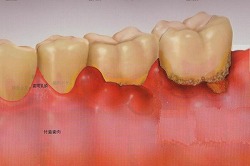

歯周ポケットが6mm以上で、歯槽骨の破壊がかなり進んだ状態。

重度歯周炎では、プラークや歯石が多量に沈着し、歯槽骨が大きく溶かされています。歯ぐきから出血、排膿を伴い、口臭がします。歯は歯槽骨の支えを失い、大きく動揺します。物を噛むと力を支えきれず、痛みがでたり、力が入らず噛めないといった症状が起こります。

さらに進行すると、歯が自然に抜けてしまいます。

重度歯周炎の症例です。歯石が多量に付着しており、歯ぐきが下がり、歯がくらぐらしています。

歯が支えを失って前に移動し、歯と歯の間に隙間ができています。

細菌が顎の骨の奥深くまで侵入し、歯槽骨がほぼ歯根の先端まで破壊されています。